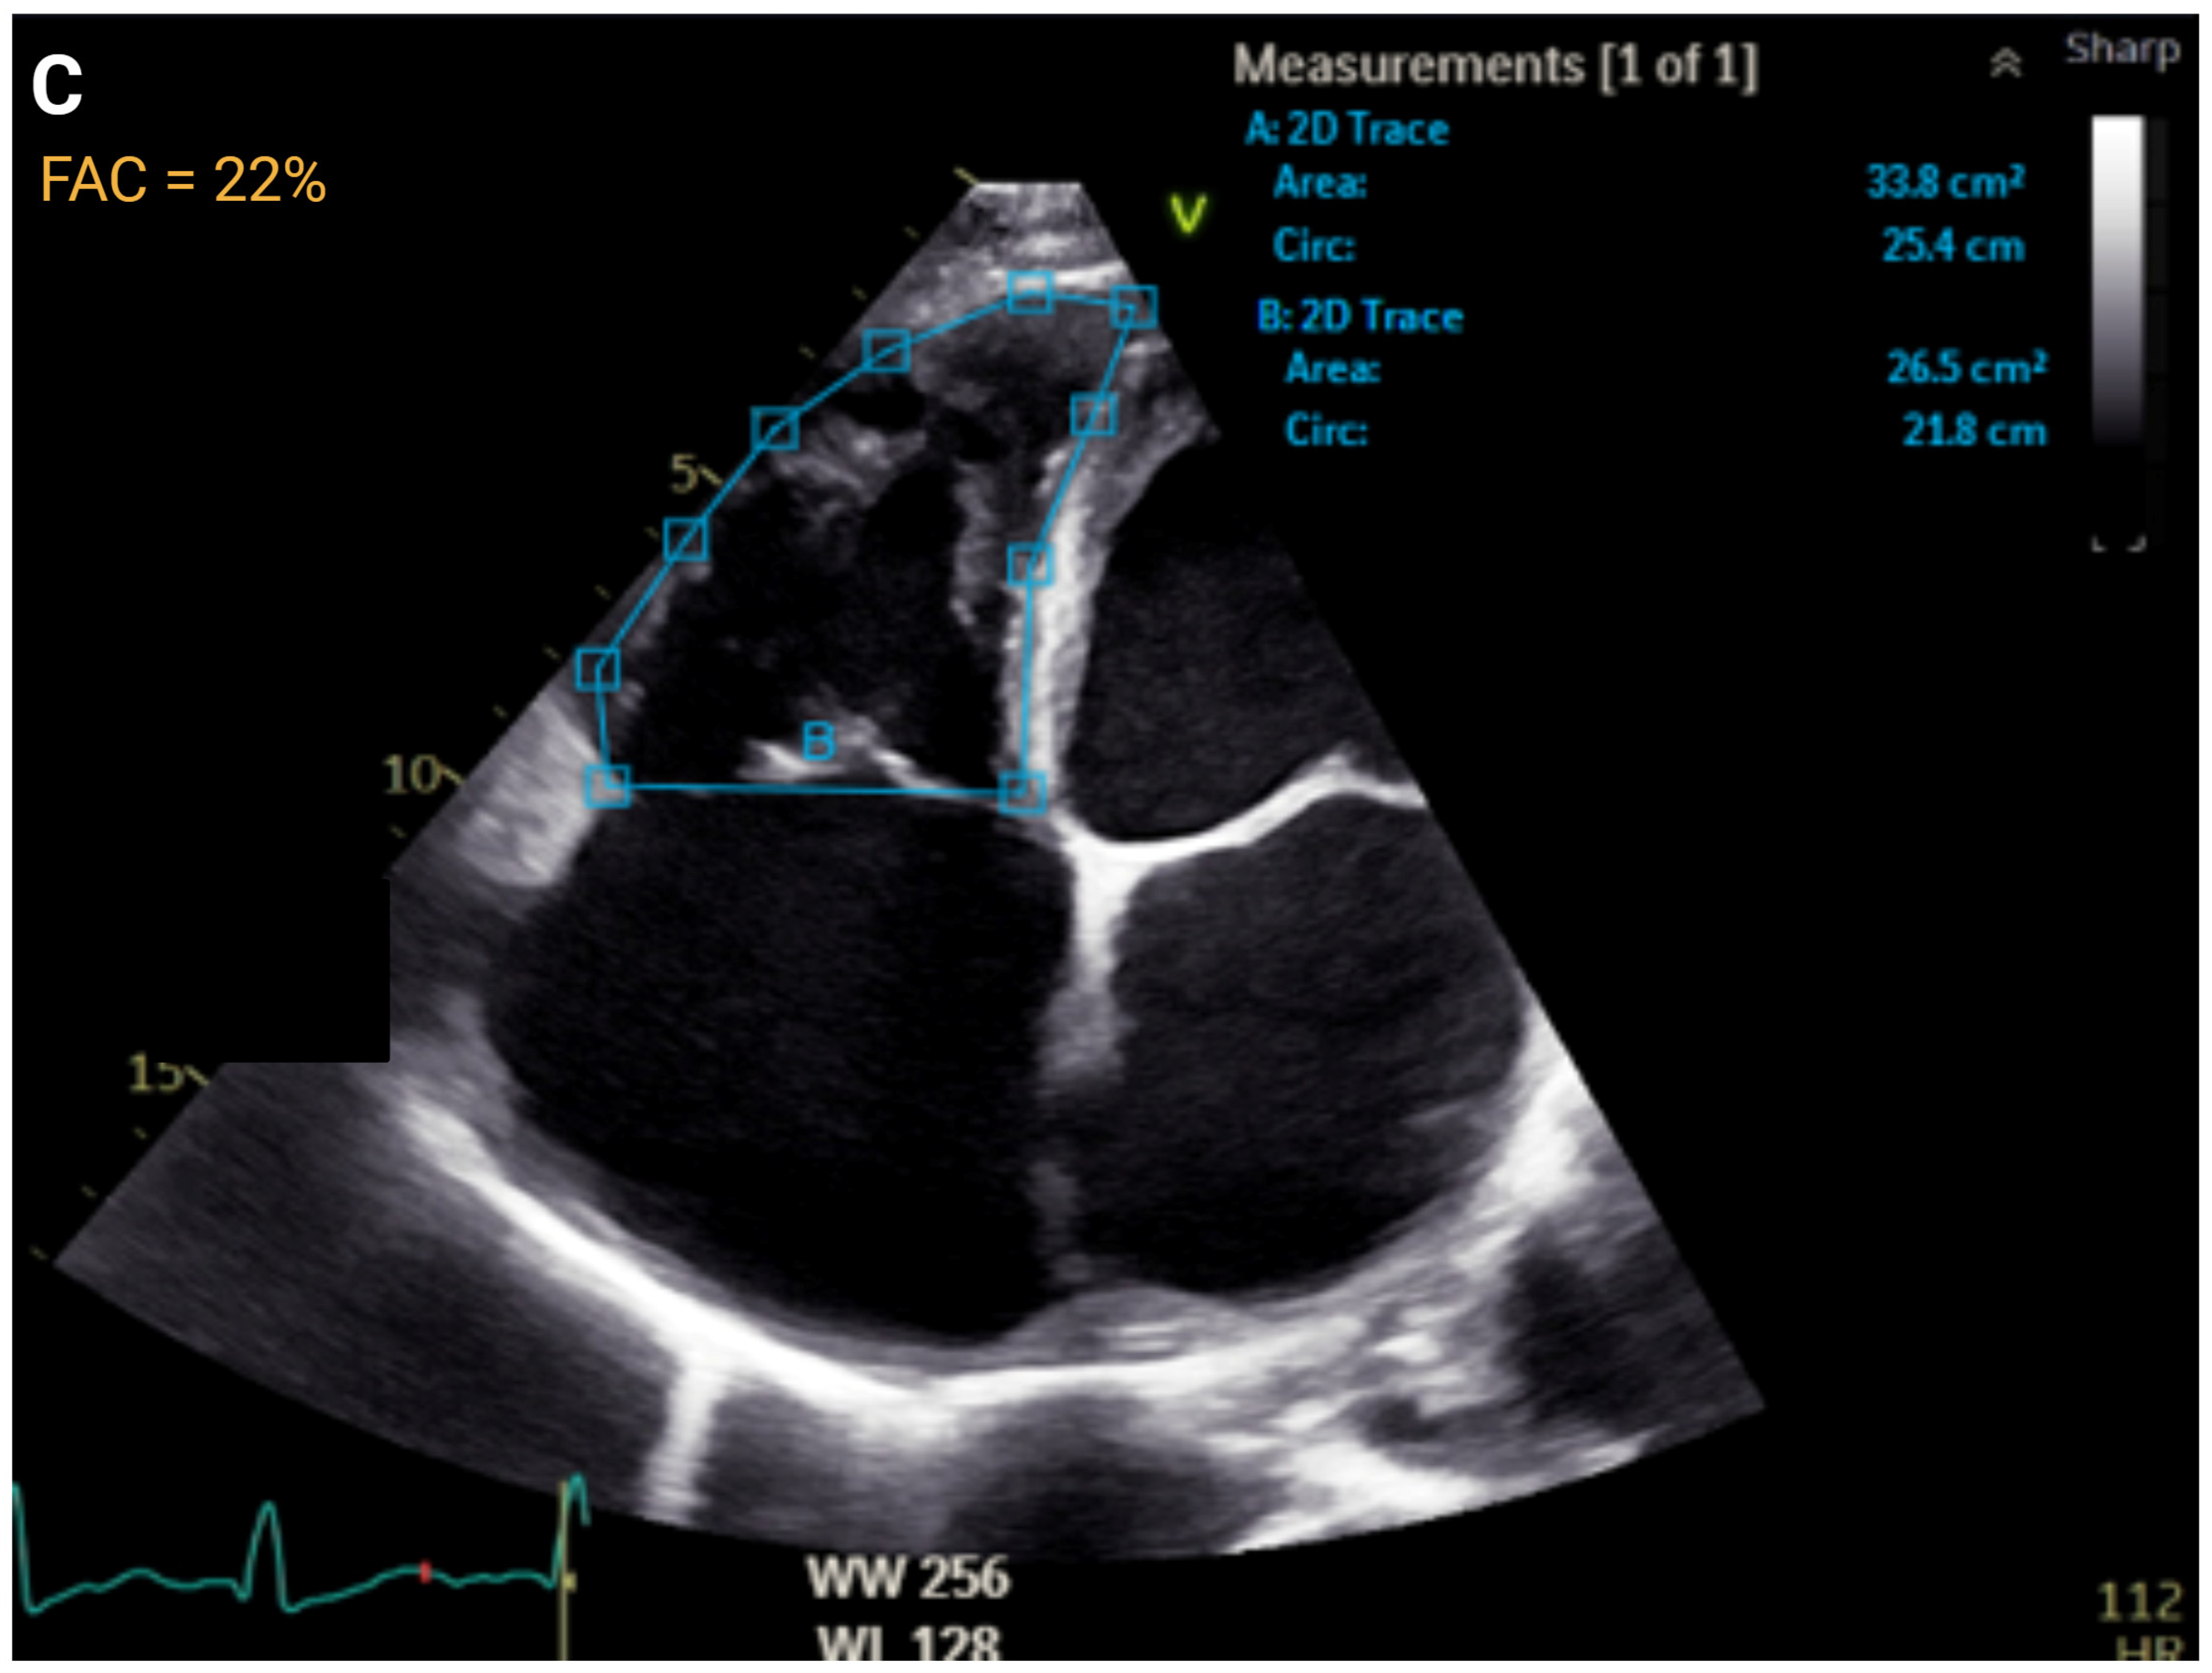

| Right Ventricular Systolic Function | ||||||

| FAC, % | >35 | ≤35 to >29 | ≤29 to >22 | ≤22 | r = 0.55 to 0.77 | AUC = 0.83 |